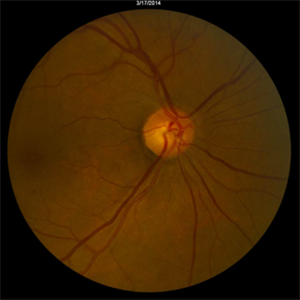

Radiation Retinopathy

Mar 12 2016 by David Callanan, MD

55-year-old with background diabetic retinopathy that developed renal cell carcinoma. Underwent radiation to left orbit. BDR in right eye

Condition/keywords: radiation maculopathy